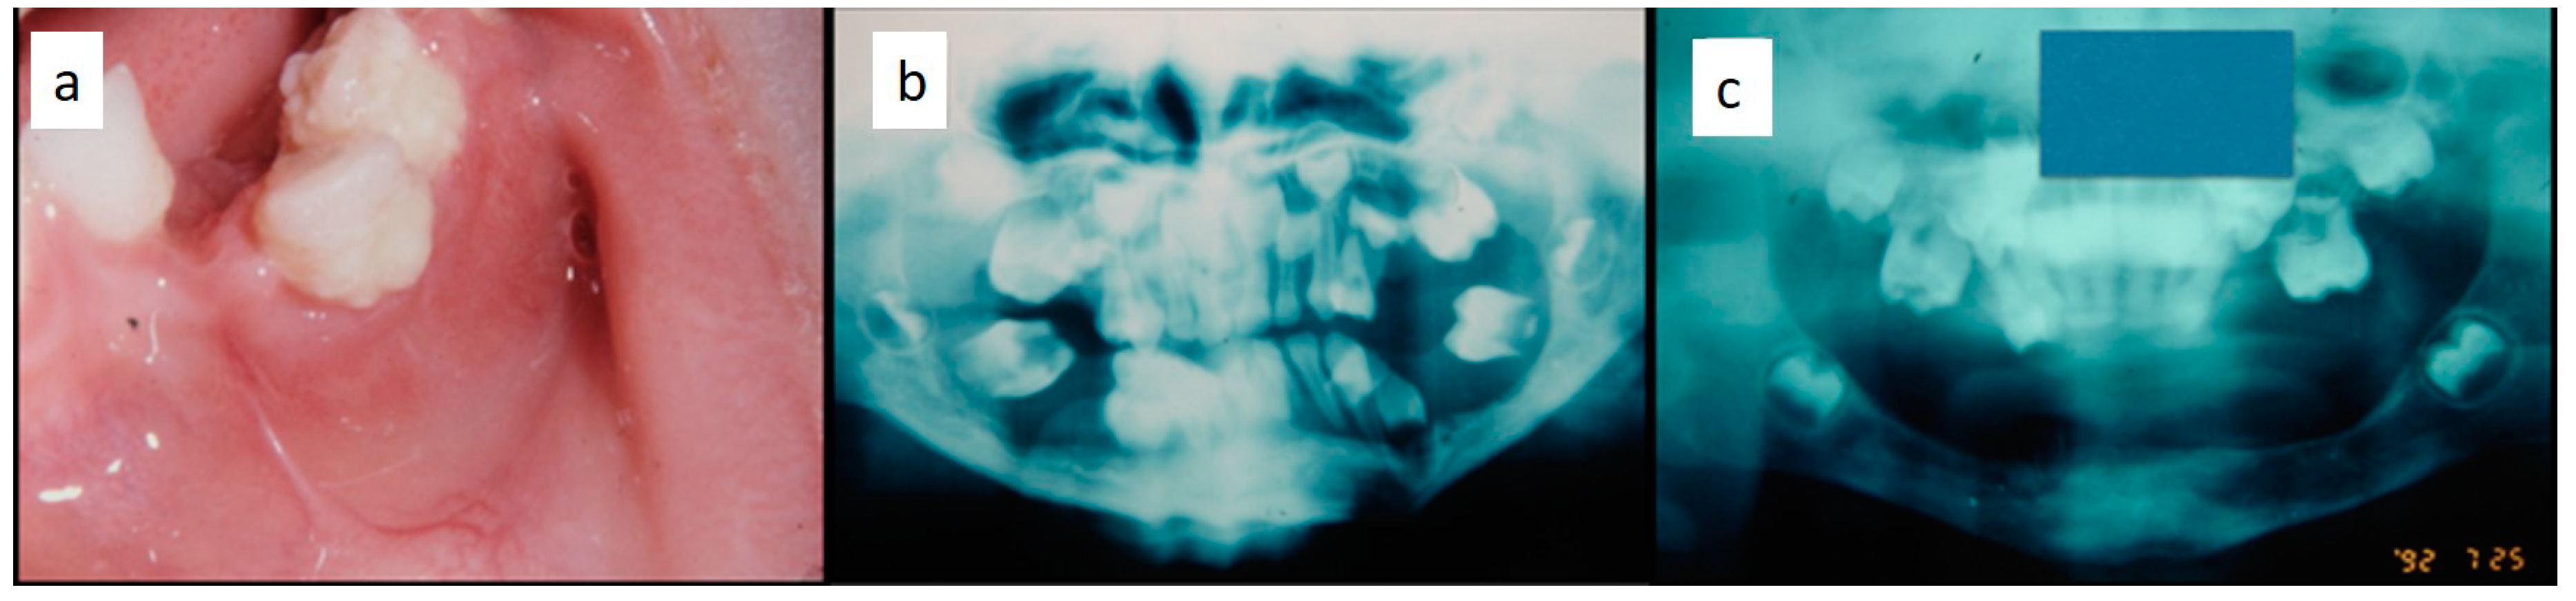

Nine patients were affected by single eosinophilic granuloma of the mandible and two of the maxilla (0–10 A; 10–18 C). Inflamed, hyperplastic, painful and often ulcerated gingival lesions were common findings in 22 cases (0–10 A; 10–18 B) (Figure 1). They were associated with deciduous teeth mobility and/or dislocation with gingival probing and periodontal bone loss in 18 cases, and to premature teeth loss with dislocation of the permanent teeth follicles and bone lesions (single or multiple) in nine cases (0–10 B; 10–18 A) (Figure 2a–d). Focal gingival swelling (often with superficial ulceration) occurred in patients with single lesion of the jaws (five in the maxilla and three in the mandible), all appearing as radiolucency with well-defined borders but, however, with rapid bone erosion (0–10 A; 10–18 C). Single lesions of the palatal mucosa were detected as the first sign in six patients (0–10 A; 10–18 B), generally appearing as reddish or strawberry gingivitis with periodontal involvement and/or complete diffusion to the palate (0–10 C; 10–18 B) (Figure 3a,b). Nine patients showed diffuse lesion of the mandible with a progressive resorption of the alveolar bone with the characteristic “floating teeth” appearance (0–10 B; 10–18 A); in six cases, localized lesions of the maxilla were synchronously detectable (0–10 C; 10–18 B) (Figure 4a,b). In addition, patients with periodontal involvement had in common a delayed diagnosis of several months as they received treatments for gingival/periodontal diseases but were unresponsive to each one. The resorption of dental roots has never been observed on either deciduous or permanent teeth. Paresthesia, due to compression of the inferior alveolar nerve, was observed in only three cases, while in six instances a pathological fracture of the mandible occurred (0–10 A; 10–18 C) (Figure 5a–c), both resulting in expansion of an osteolytic lesion. Submental, submandibular and lateral-cervical lymph nodes involvement was associated with oral lesions in 12 cases (0–10 B; 10–18 B). Adjunctive radiological examination revealed lesions of the skull in 14 patients and, respectively, two of the parietal bone (Figure 6a), two of the temporal bone, one of the zygomatic bone, and three of the orbit (0–10 B; 10–18 C). Otitis (media or externa) was referred or detected in four instances, cutaneous rush in nine (0–10 B; 10–18 C) (Figure 6b), exophthalmia in two (Figure 7a,b), while data about the contextual presence or subsequent onset of insipidus diabetes were available only in eight cases (0–10 B; 10–18 C).

Figure 4. (a,b): Involvement of the entire periodontium, gingiva (a) and alveolar bone (b), of the mandible and maxilla causing premature loss of deciduous teeth; impressive bone resorption and following difficulties in permanent teeth development; the patient was a 11-year-old male, receiving treatment for gingival inflammation and teeth mobility for several months, thus causing a delayed diagnosis of LCH.

Children 07 00104 g004